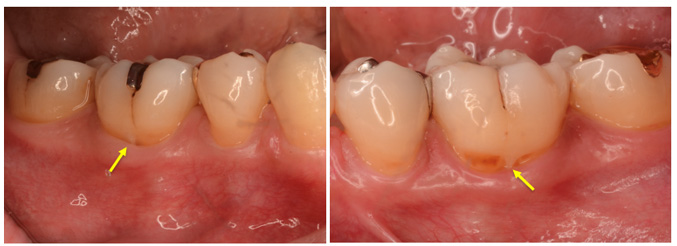

![]() 図T-3-29 歯の形態異常 エナメル突起(エナメルプロジェクション) 上下顎第1 大臼歯部にみられたエナメル突起(エナメルプロジェクション〈矢印で示した突起部〉). 根分岐部の発生期の先天異常であるため,左右対称にみられる. |

![]() 図T-3-29 歯の形態異常 エナメル突起(エナメルプロジェクション) 下顎第1 大臼歯部にみられたエナメル突起(エナメルプロジェクション〈矢印で示した突起部〉). 根分岐部の発生期の先天異常であるため,左右対称にみられる. |